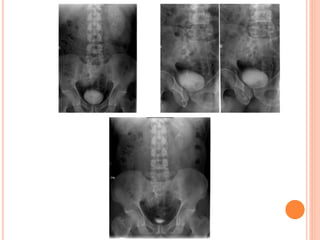

PRELIMINARY IMAGING

Preliminary abdominal imaging usually

precedes catheterization.

VCUG is commonlyperformed in children with prenatally diagnosed hydronephrosis, urinary tract infections, and voiding abnormalities. The procedure should include assessment of the spine and pelvis; masses or opaque calculi; bladder capacity, contour, and emptying capability; presence and grade of reflux; and urethral appearance.

PRELIMINARY IMAGING Clinical dataand results of prior imaging studies should be reviewed before starting the examination. Preliminary abdominal imaging usually precedes catheterization.